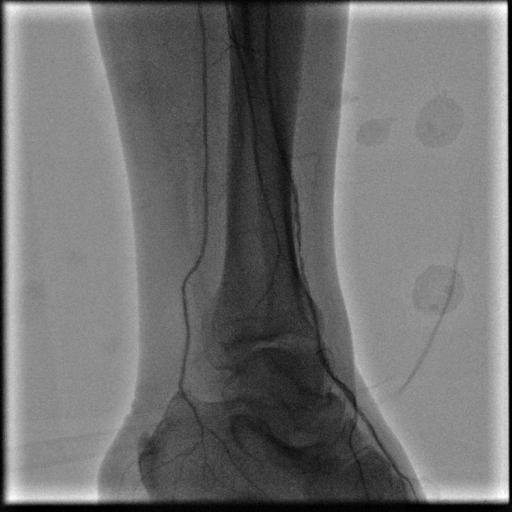

Bacak ağrı ve yanma ve nabız zayıflığı şikayeti ile başvuran hastanın MR Anjiyosunda bacak ana damarının tam tıkalı olduğu görüldü çekilen MR da hastanın şikayetinin asıl nedeninin Bacak Damar Tıkanıklığı olduğu anlaşıldı. Stent uygulaması ile damardaki darlık açıldı. Hastanın takiplerinde bacak ağrısının, yanmasının ve nabız zayıflığının tamamen geçtiği görüldü.